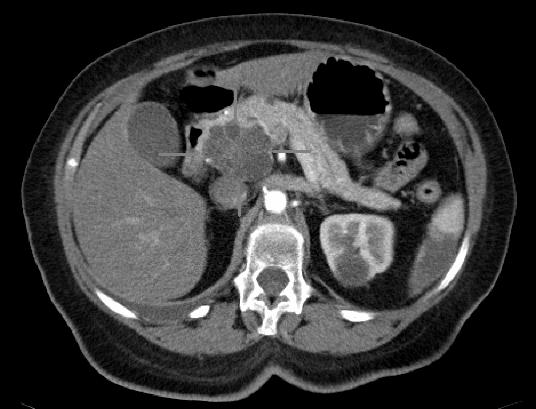

美国有超过62,000人将在今年年底被诊断为胰腺癌,其中绝大多数有一种致命的侵袭性亚型被称为胰腺导管腺癌(PDA)。PDA影响90%以上的胰腺癌患者,平均5年生存率低于10%。近期研究发现MSRA表达水平在PDA细胞中作为原发癌生长和转移扩散之间的“分子开关”发挥作用,为切换这种分子开关来阻断疾病向其他器官的扩散的治疗方法提供关键见解。